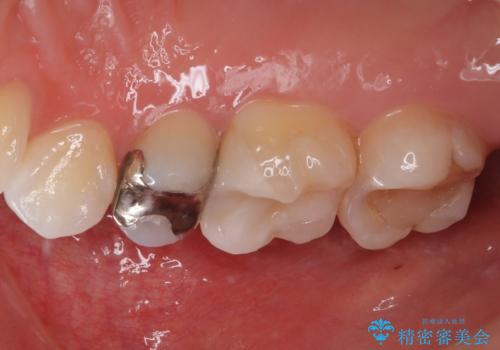

歯と歯茎の間に圧排糸と言われる糸を入れてシリコーン印象材にて精密な型どりをしました。

セラミックインレーの装着時には、唾液の侵入を防ぐために、ラバーダム防湿を行いました。